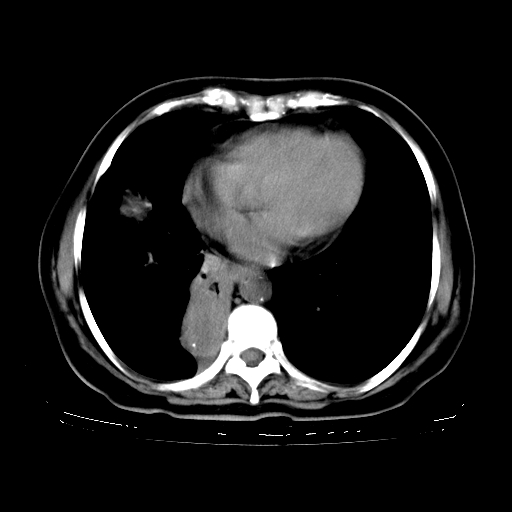

女,70岁,咳嗽、咳痰一个月,低热一周。

1、右肺占位,考虑周围型ca 。

2、右下肺软组织密度肿块影,考虑肺隔离征。

3、两肺肺结核(右肺下叶背段及左肺)。

4、主动脉夹层。

5、右侧少量胸腔积液。